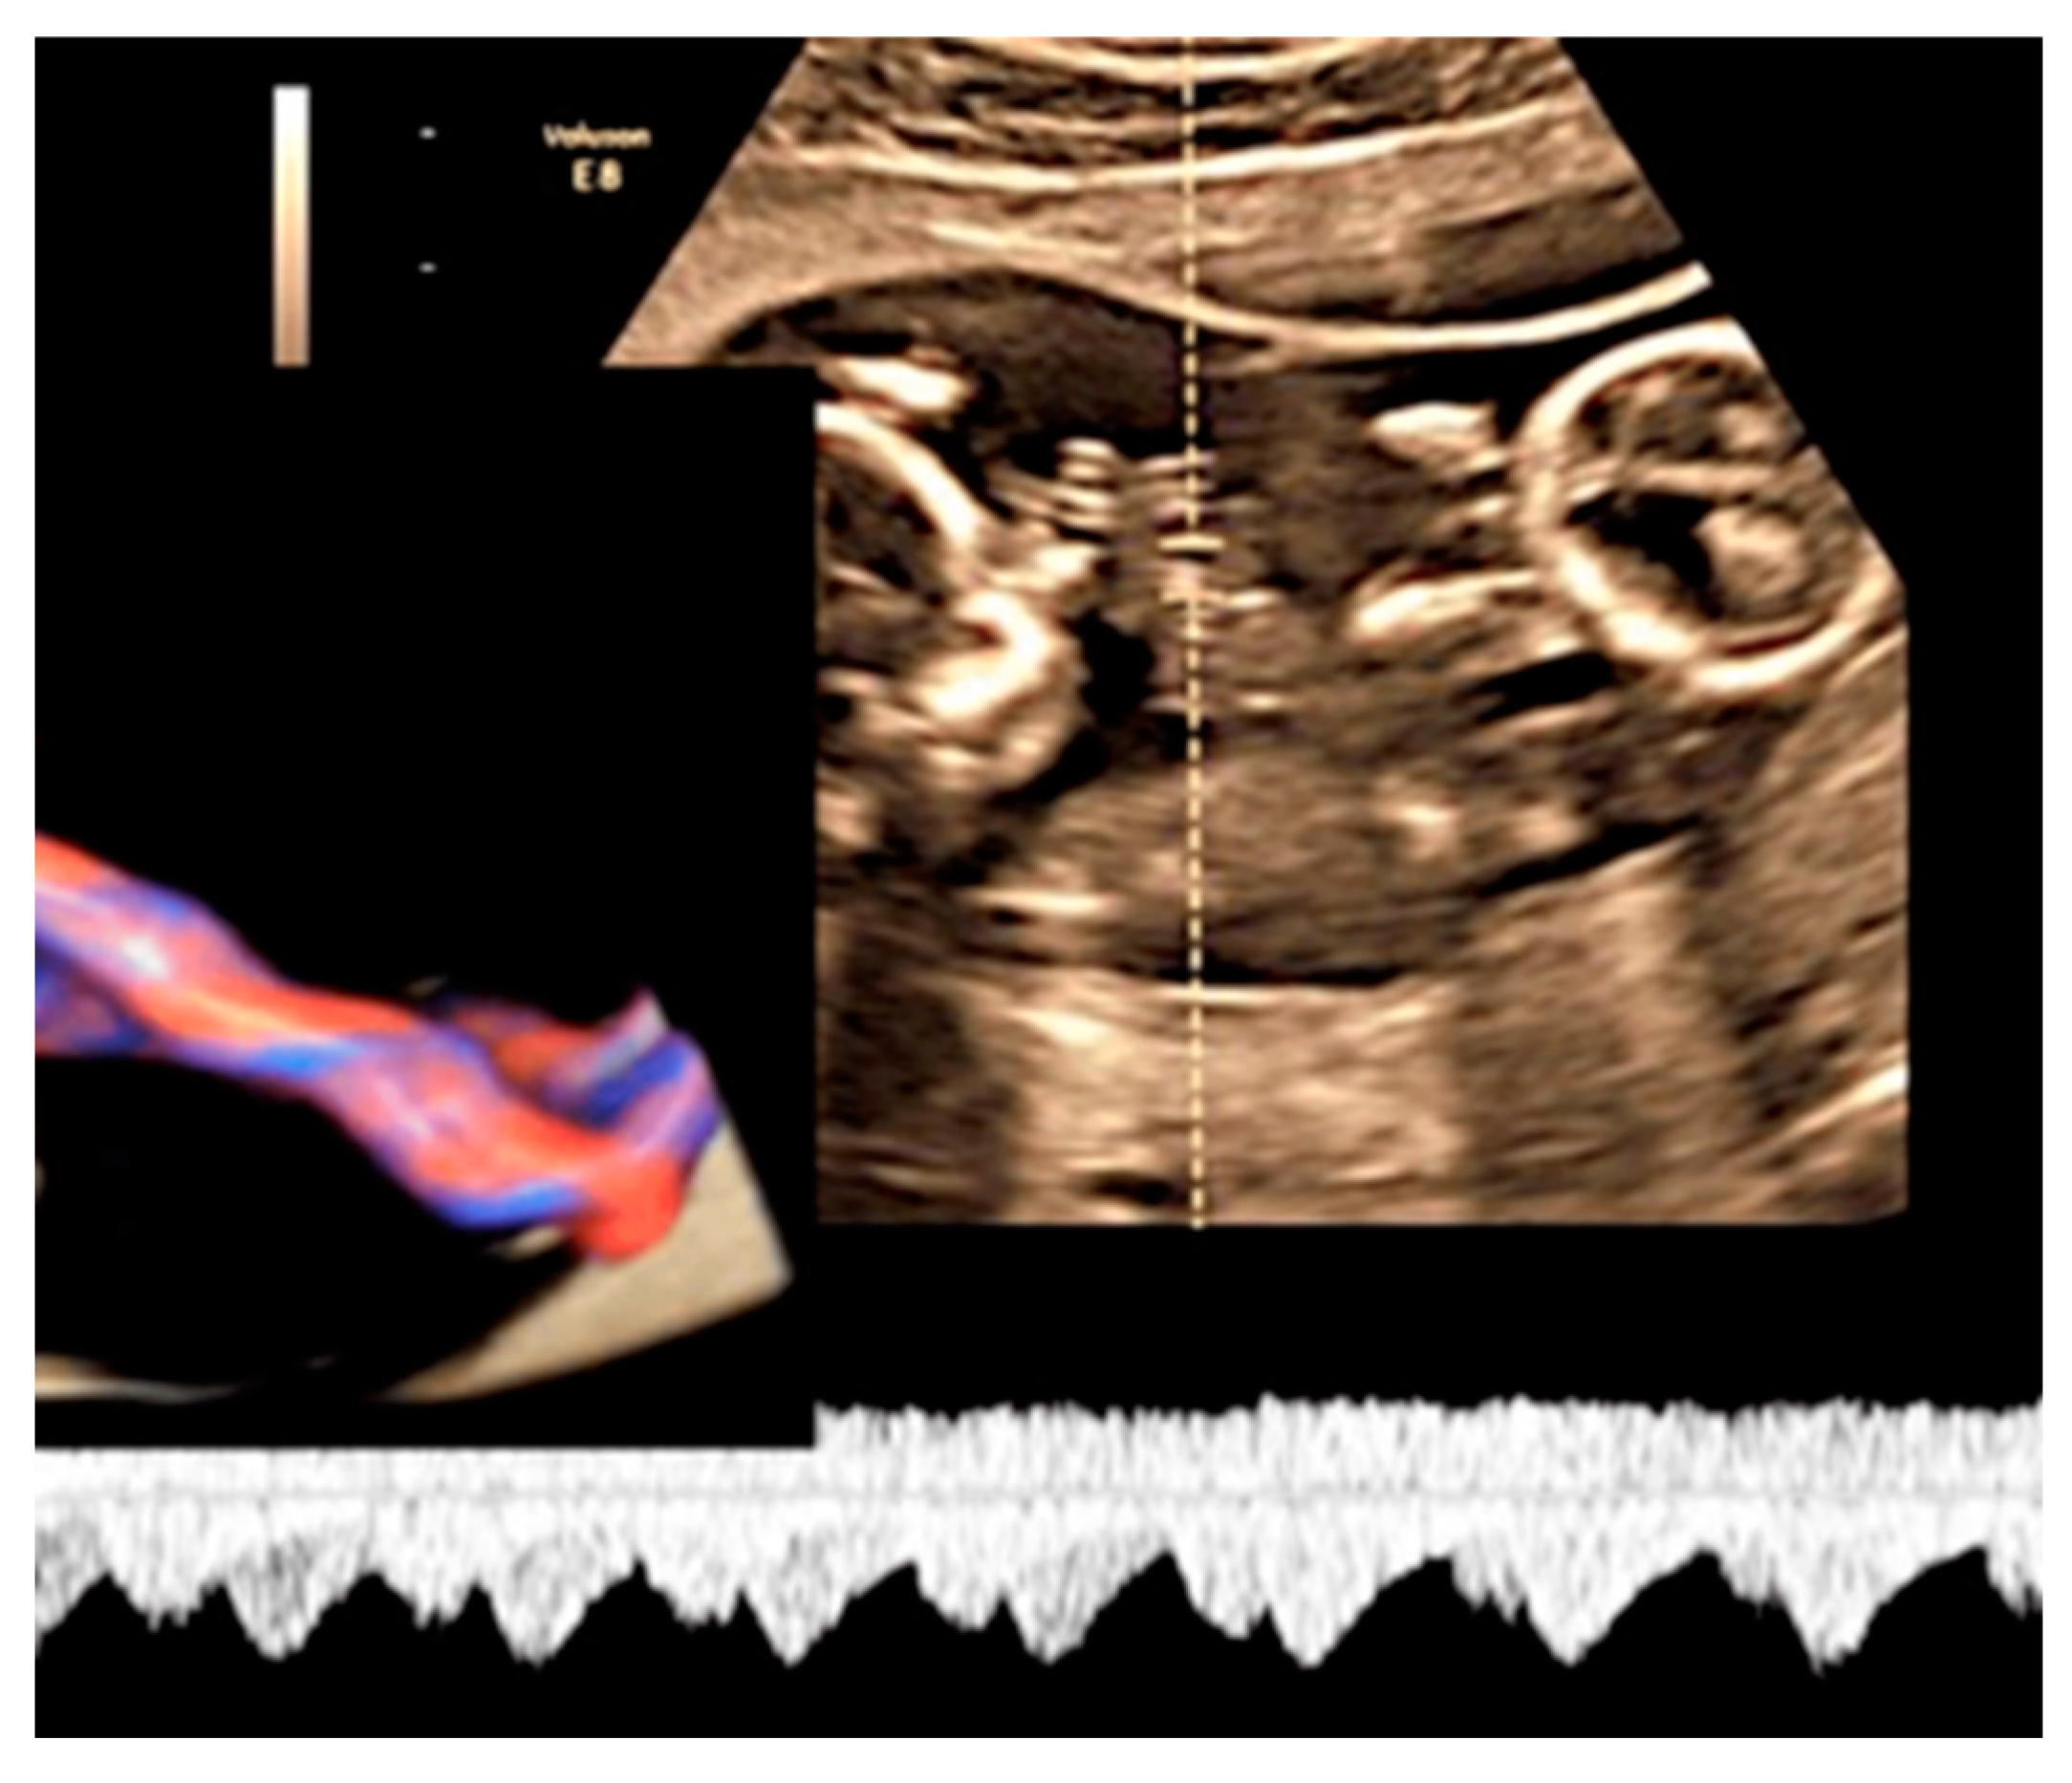

3.2.6. Umbilical Cord Entanglement

Umbilical cord entanglement is a condition exclusively of monoamniotic twin pregnancies and occurs because both umbilical cords insert close to each other in the single placenta [47]. The entangled cords can cause vascular damage for one or both fetuses and lead to fetal demise [47]. Diagnosis can be made through the visualization of a branch pattern on color Doppler ultrasound at the level of the entanglement, and an end systolic notch seen on the umbilical artery waveform reflects vascular compression or narrowing [47,61] (Figure 25).

Figure 25.

MCMA twin pregnancy. Cord entanglement can also be detected with the “galloping horse sign” that involves identifying two distinct waves signals with different heart rates obtained by sampling an apparently unique umbilical cord with pulse wave (PW) spectral Doppler ultrasound.